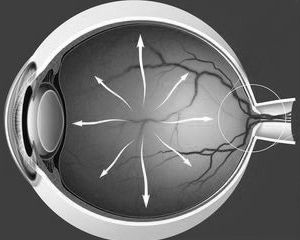

В очному яблуці при нормальних умовах у здорової людини існує певна кількість рідини, яка служить в якості мастила для рогівки і дає необхідні поживні речовини. Збільшення внутрішньоочного обсягу цієї рідини призводить до підвищення тиску, а зменшення - до його зниження, при цьому симптоми і причини цього відхилення можуть бути різними.

- відшарування сітківки,